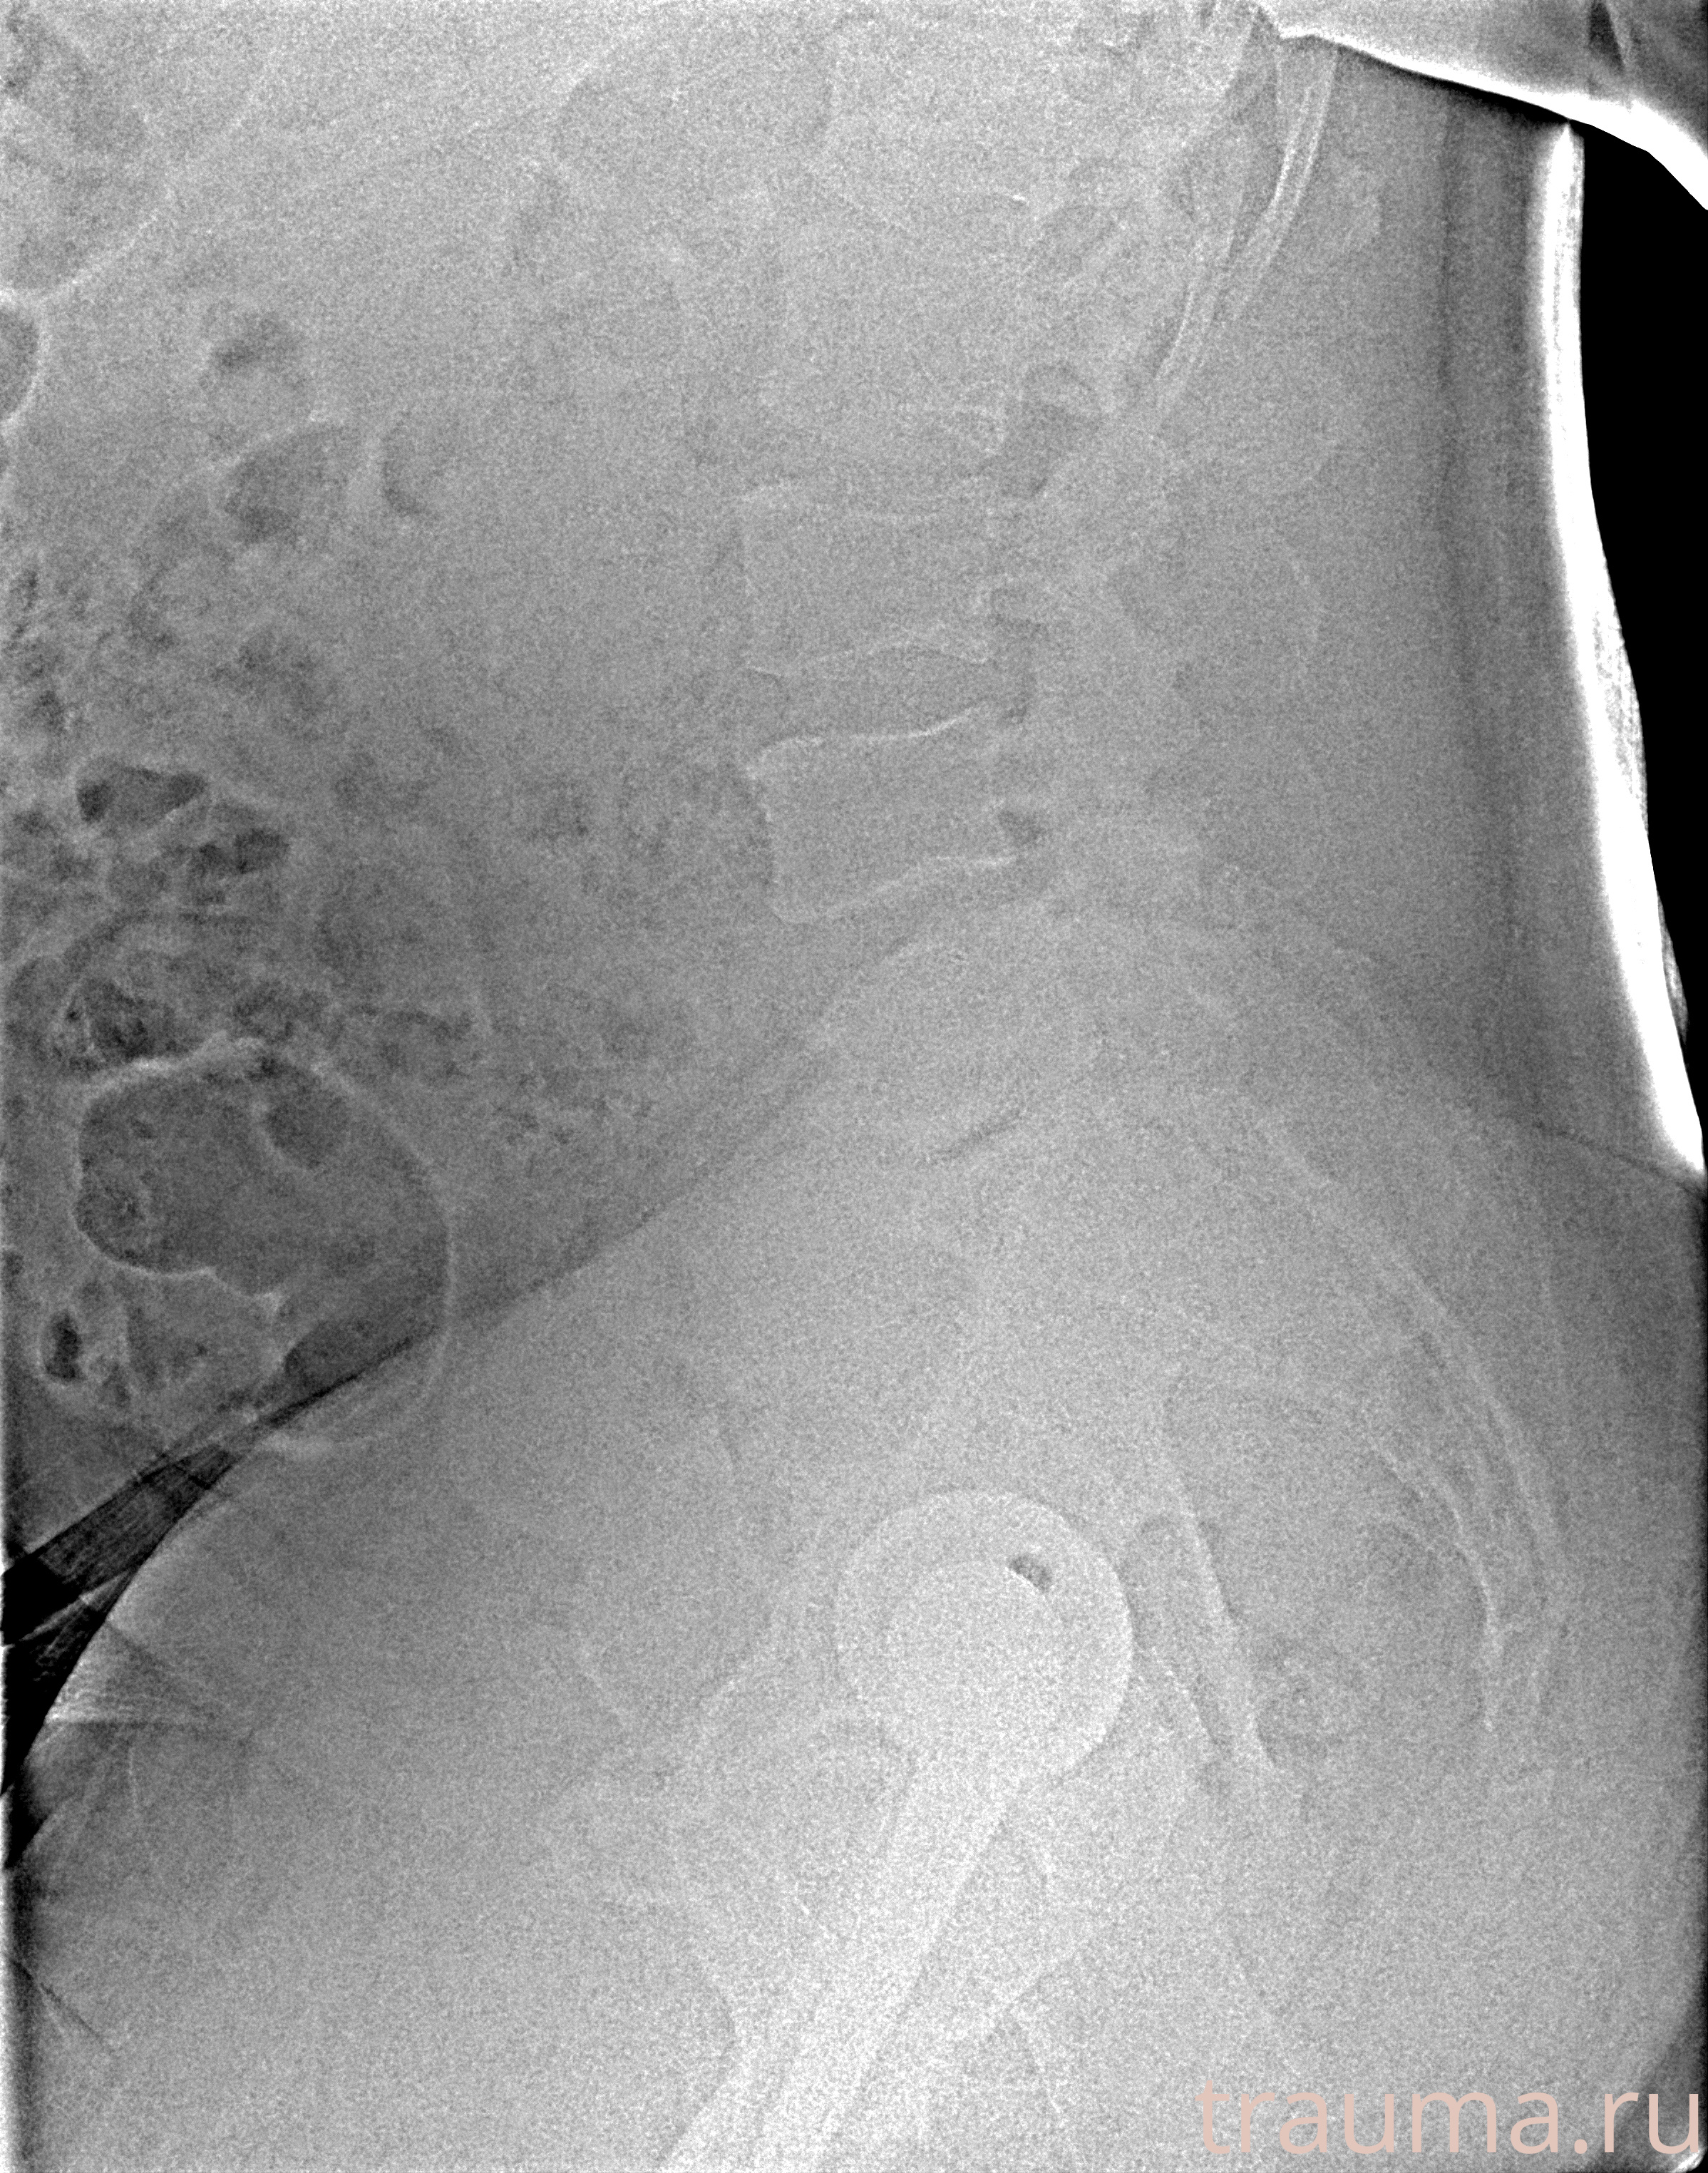

Рентген на дому: по вашему адресу приезжает врач-рентгенолог, травматолог-ортопед с мобильным рентгеновским аппаратом, проводит диагностику травмы или заболевания, делает необходимые рентгенограммы, дает рекомендации по дальнейшему лечению. Получить качественные снимки в домашних условиях возможно благодаря уникальной методике, разработанной МосРентген Центром для института  Склифосовского